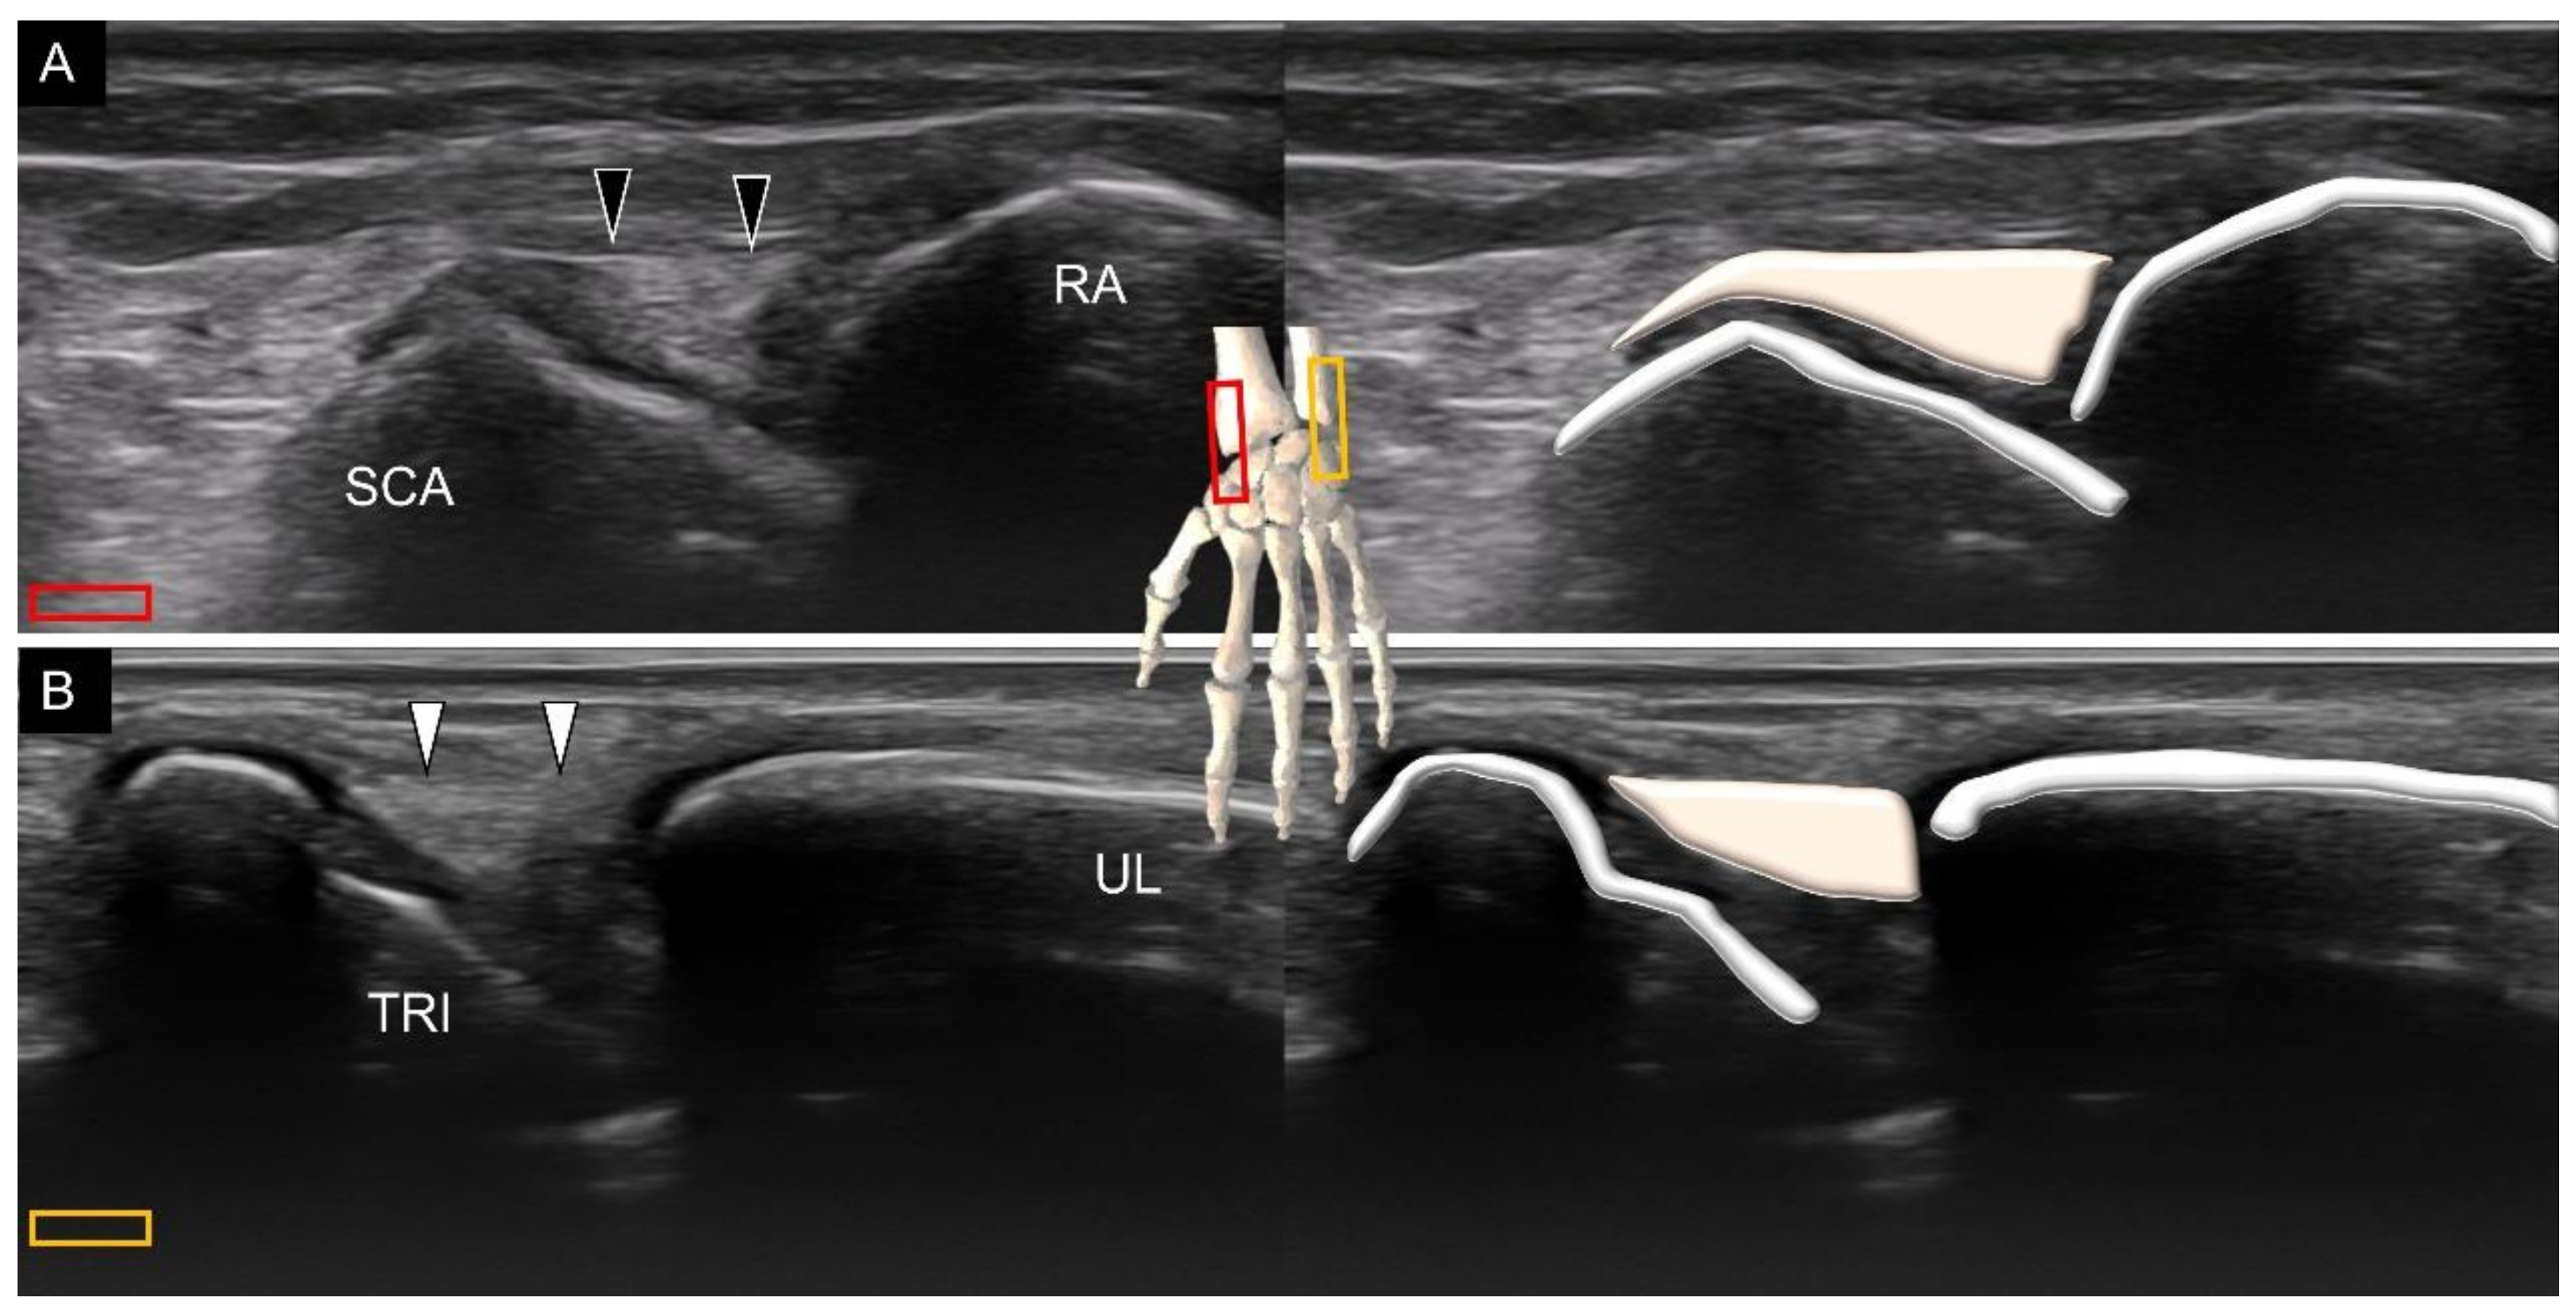

3.3. Attachment to the Triquetrum

7. Sonoanatomy of Wrist Collateral Ligaments